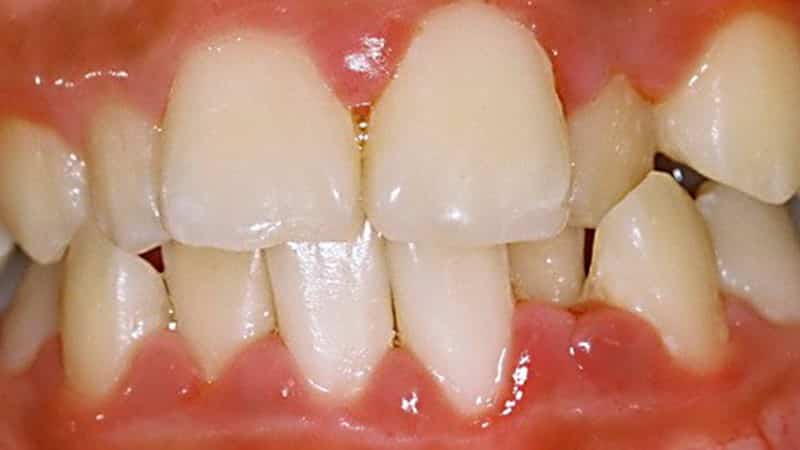

В некоторых случаях у ребенка может наблюдаться повышение температуры. Врач сможет легко установить диагноз всего лишь по результатам визуального осмотра. Гингивит всегда проявляется покраснением десен, отечностью тканей, образованием ранок и язв, а также кровоточивостью.

Наиболее часто у детей встречается катаральная форма заболевания. Она сопровождается дискомфортом в области десен, жжением и неприятным запахом изо рта. Во время еды может наблюдаться кровоточивость. Ребенок может не испытывать таких симптомов, как боль или повышение температуры, но часто игнорирует необходимость чистки зубов.